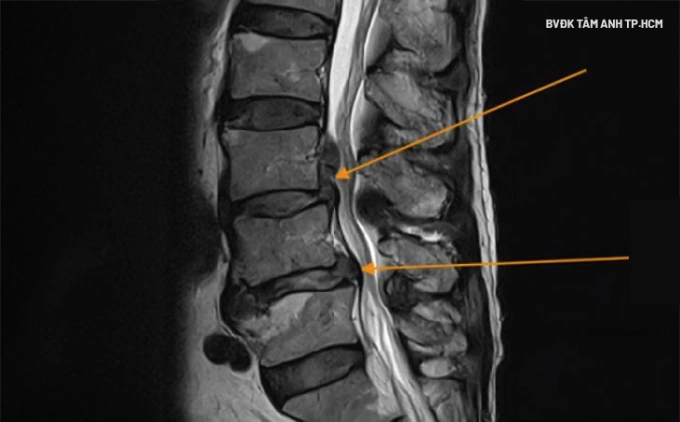

Phim chụp MRI cho thấy vị trí đốt sống thắt lưng bị tổn thương của anh Duy. Ảnh: Bệnh viện Đa khoa Tâm Anh

Anh Duy đến Bệnh viện Đa khoa Tâm Anh TP HCM khám trong tình trạng đau lan xuống chân, tê bì, đi lại khó khăn. Kết quả chụp MRI phát hiện thoát vị đĩa đệm cột sống lưng L3L4 và L4L5.